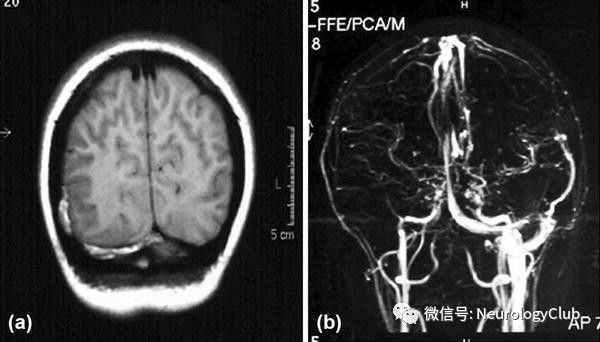

(图24:a:T1WI;b:MRV;可见右侧横窦血栓形成)